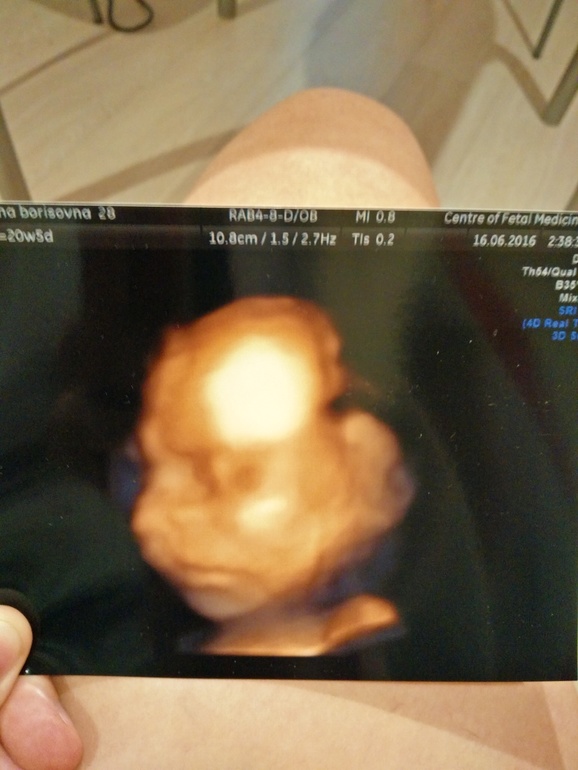

Сегодня прошла второй скрининг. Делала в Центре медицины плода на Ваське у Порозовой Е.Н. Идём срок в срок. Все в норме. Только пока все ещё плацента низко, ну хоть зев не перекрывает, только подходит к нему вплотную. Но я уверена, что она вскоре поднимется)) Сын оказался с характером. Категорически отказывался позировать. Меня промурыжили 2 (!!!!!!) часа. Лежал все время неудобно. Не давал смотреть лицо, сердце. Убегал от датчика. Два раза погулять отправляли. Шоколадом кормили (сразу воды стал глотать))))) 361 грамм живого веса, а вредности .... Ну весь в отца)) И фоткаться, как и он, не любит, поэтому 3D (с 4ой попытки) получилась мягко говоря не очень. И ещё у нас, кажется, римский профиль... Нос мужа кажется... Ну для мальчика сойдёт. А вообще, доктор сказала, что по этому 3D не стоит оценивать и предполагать внешность)) Прилагаю фото себя и сынули.